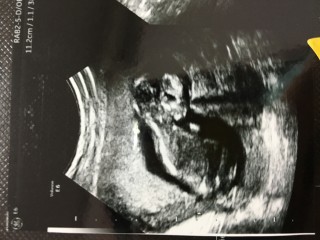

写真:12w1d:りぷとんさん

2022年9月 12w1d 7.5cm

高齢出産なので、NIPT(出生前診断)と胎児ドッグを受けてきました。

小さい手や足を一生懸命動かしていて本当に可愛かった!辛いつわりも吹っ飛びます。もう膀胱でおしっこもちゃんと作られていたり、この段階で分かってしまうのがすごい!9年前の一人目の時よりレベルが上がっていて終始驚いてました笑

12w1d BPD22mm

4日ほど大きく、心拍も鼻の骨や指や大腿骨もしっかりしてピョコピョコ動いてた!もう愛しい!!まだつわりはあるけどお母さんも頑張るよ♪